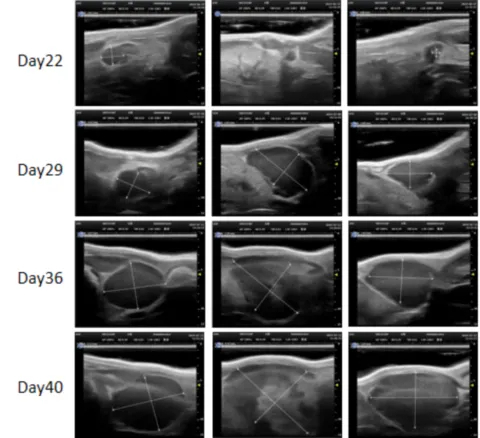

PDX Model (Growth Curve)

²¿·ÖÃÀ¸ß÷PDXÔλģ×Óչʾ